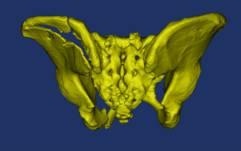

面对这一困境,市四医院骨一科手术团队联合数字医学中心,通过术前的骨盆模型三维重建,模拟复位,设计骶髂螺钉导航模板并3D打印,术中通过导板引导,成功置入骶髂螺钉,为患者进行手术治疗。

骨盆术前三维模型和模拟复位--正位前面观